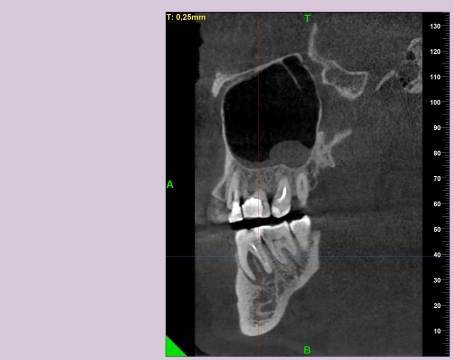

КТ от 28.05.2024

28_05.24(2).jpg.0ffa1febe861106733e1de830afbe6f4.jpg28_05.24-1(2).jpg.9c45d7be16aeed505bd413ce9bc6e69e.jpg28_05.24-2.jpg.a728a7d7e6213c1c8302b43adc89e4d0.jpg28_05.24-4(2).jpg.ac43f3448a3988c7006f74e1d0ce09da.jpg28_05.24-6(2).jpg.dd1fd85c6cc0fcd3d43bd9e71fc0d616.jpg28_05.24-8(2).jpg.885c8cb905445e9308f124fb9e5c616b.jpg28_05.24-9(2).jpg.6cceaaaa1b56d0967482c87b951fbe2d.jpg28.5.24-5(2).jpg.b2d79427a16769c9fd4f0d0911a9db8f.jpg28.5.24-7(2).jpg.f6c17f9820e72dc2708955a65a190b57.jpg28.0524-3(2).jpg.0aa9f153071766a340b428158a94ade8.jpg

Лекарство было извлечено, и каналы запломбированы гуттаперчей. Доктор предупредила, что зуб будет болеть, и прийти я должен после того, как зуб "успокоится", болевые ощущения пропадут. На третий день десна под зубом вспухла, и начала сочиться сукровица. Я решил сделать новое КТ(28.05.2024), и с результатом сходить в другие клиники для консультации. В первой мне сказали, что доктор не должна была начинать лечение, потому, что зуб идет под удаление. Во второй клинике, что попытаться вылечить можно, но изначально были допущены ошибки в лечении, и надо переделывать.

Что-то можно сделать с 46 зубом для сохранения, или он должен быть удален?